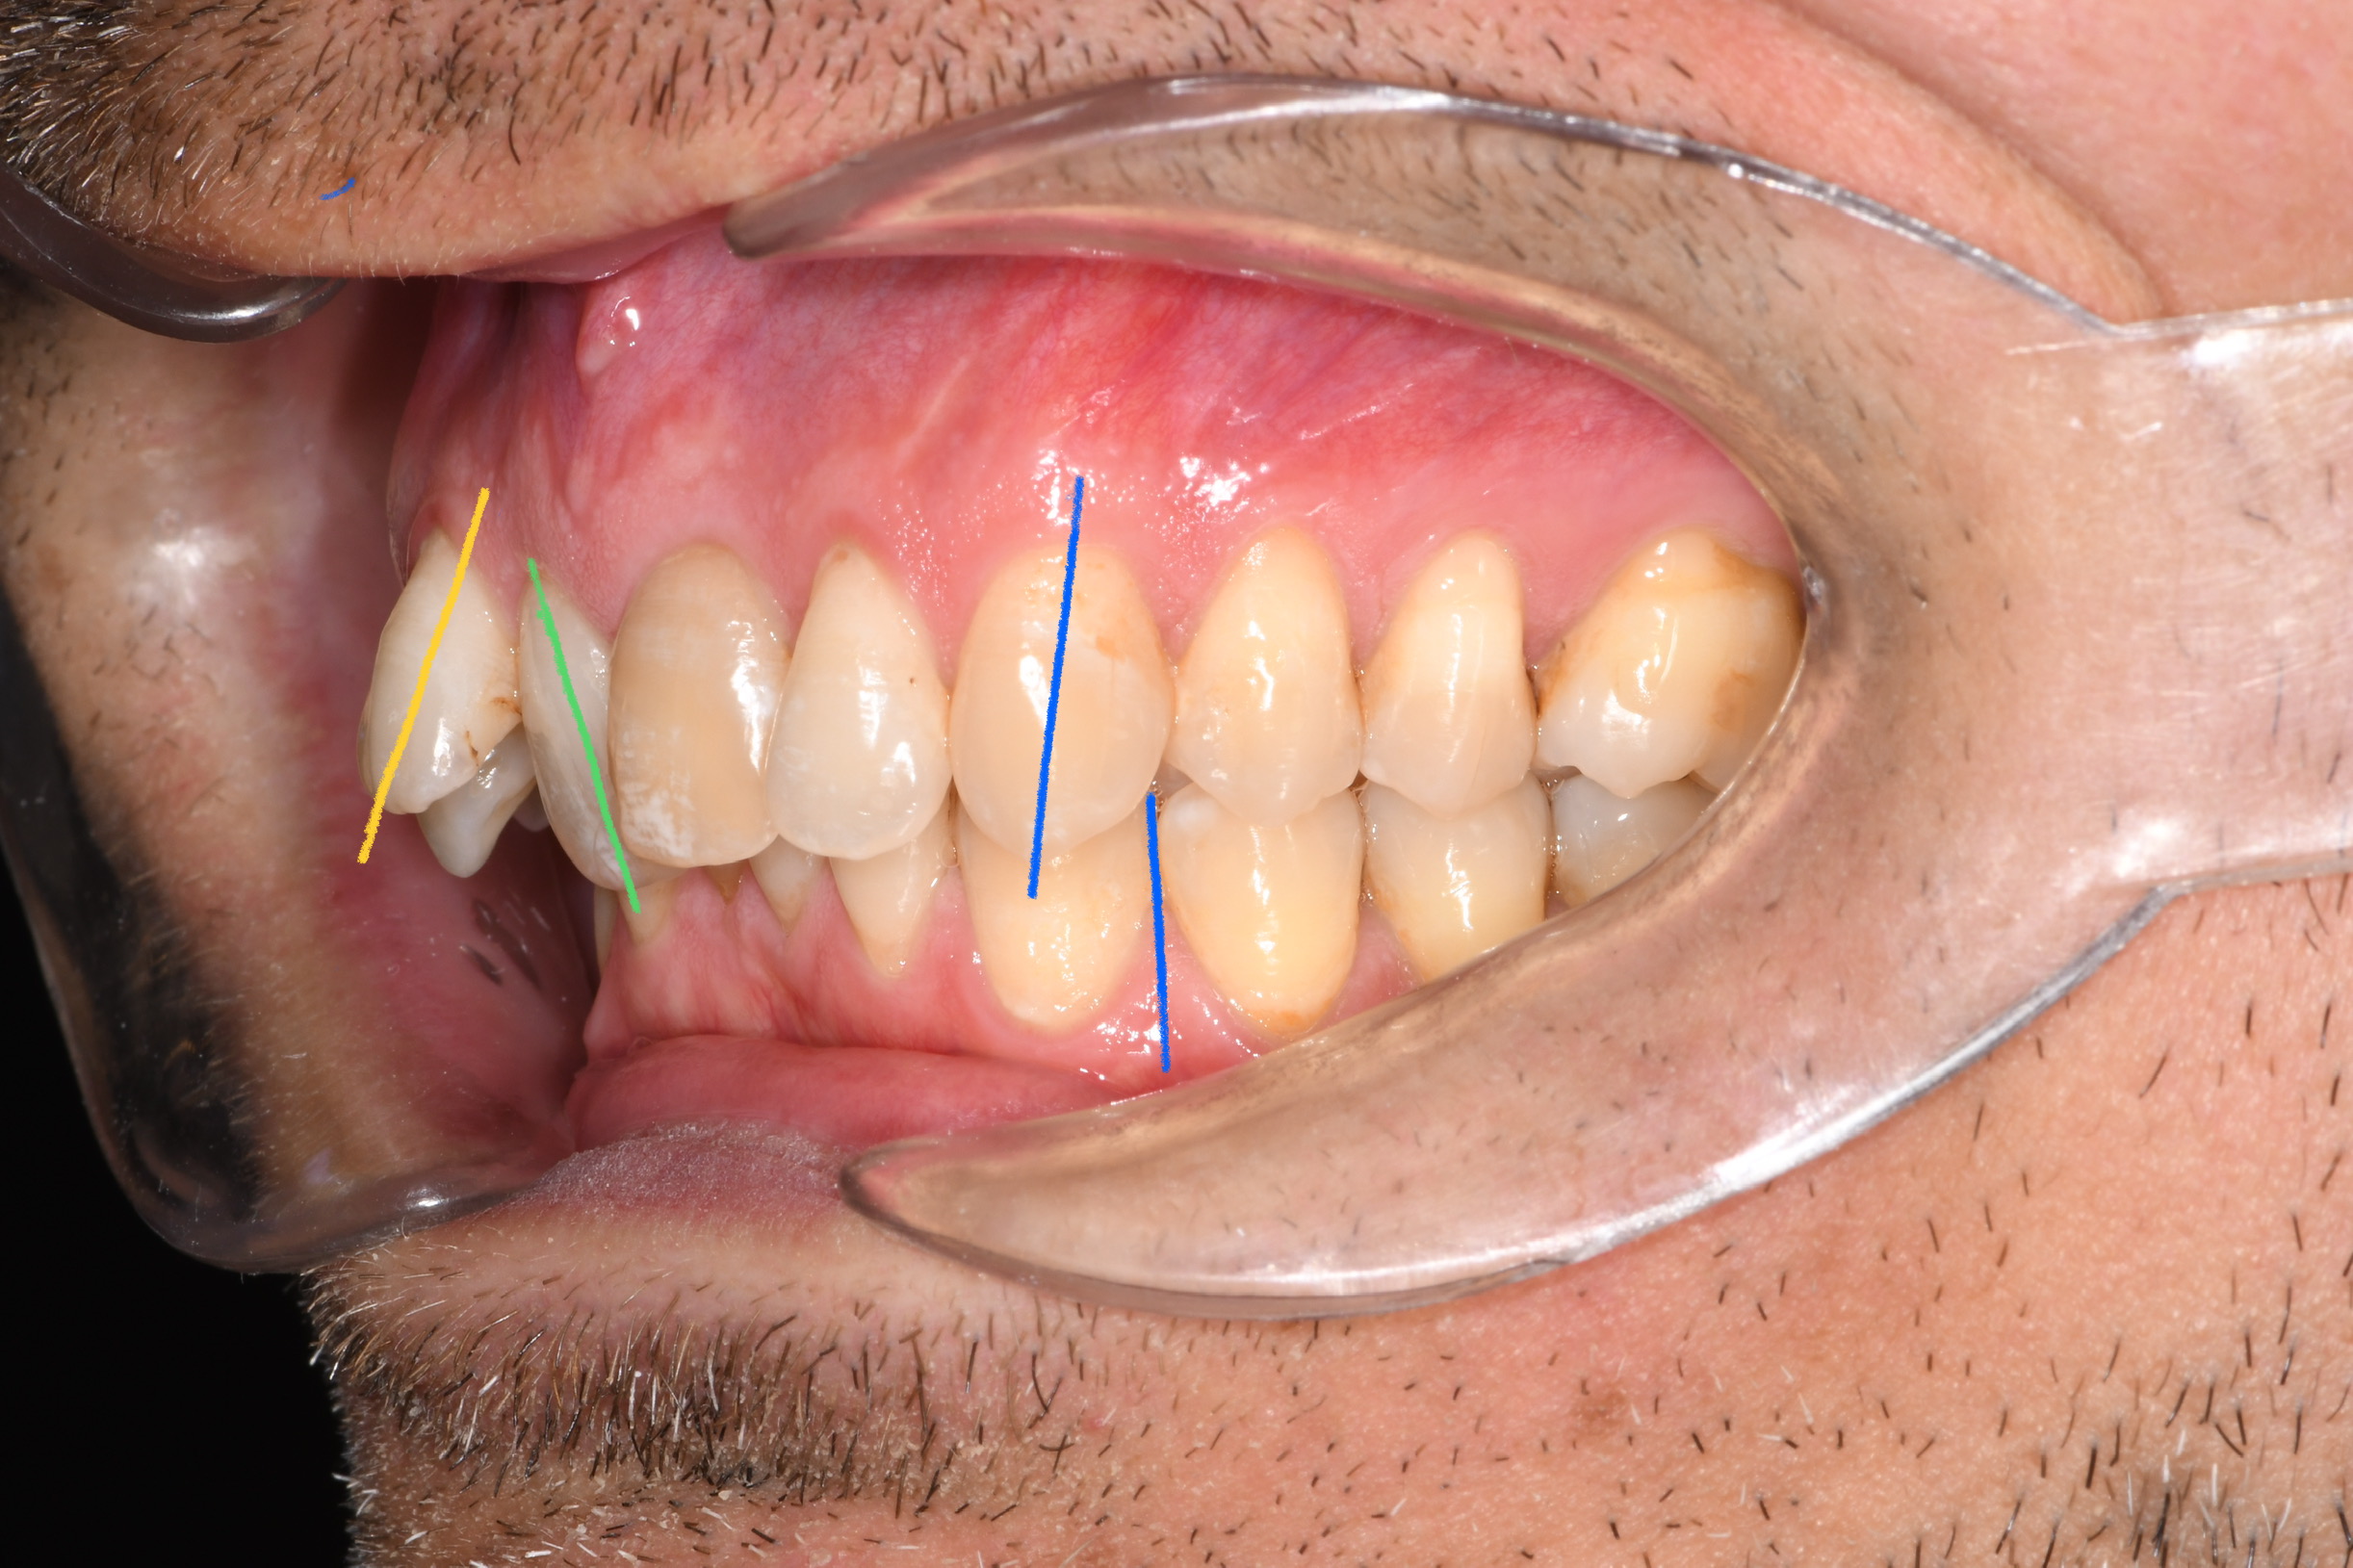

Az elmúlt évekből rengeteg szakmai referenciát tudnánk bemutatni, amelyek különböző fogszabályozási problémákat oldottak meg. Válogatva a több száz esetből, ezen az oldalon olyan képeket, információkat igyekeztünk bemutatni, amelyeknek a segítségével a jövőbeni pácienseinknek azt tudjuk üzenni: A Te fogsorod is lehet gyönyörű!

(Képeket a Pácienseink külön írásos beleegyezésével mutatjuk be!)